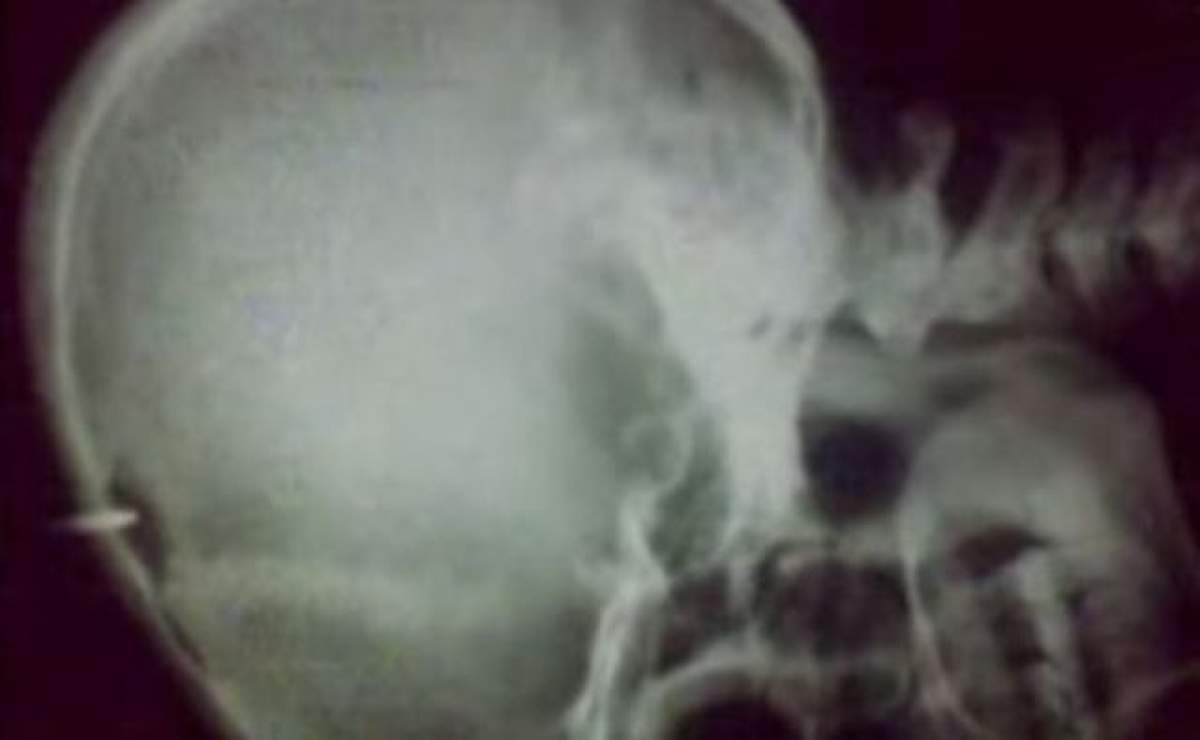

Un deţinut de la Penitenciarul Focşani care are de executat o pedeapsă de trei ani de închisoare pentru furt şi-a înfipt un cui în cap şi a înghiţit o lingură.

În urma incidentului el fiind transportat la Spitalul Judeţean de Urgenţă.Reprezentanţii spitalului spun că atunci când a fost adus la unitatea medicală bărbatul nu a colaborat, refuzând iniţial să îi fie scos cuiul, care îi străpunsese doar pielea, nu şi craniul.